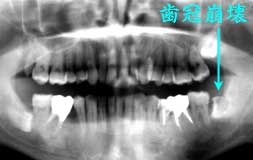

初診時 パノラマ 術中 Dental写真

|8歯冠崩壊が著しく、歯髄炎発症直前

口腔内清掃状態はやや不良だが歯石沈着は少なく、歯槽骨吸収も年齢の割には軽度。 |7および|8に深いカリエスを 認めるが、他部位は軽度なカリエスが散在する程度であった。

主訴の|7を抜髄したのち、歯周疾患初期治療とカリエス治療を行い全体の治療を ほぼ終了した段階で、最後の仕上げとして|8 を抜歯することを提案した。ほとんど粘膜に覆われた完全埋伏状態であるにも関わらず、歯冠 部分全体がカリエスで崩壊しており、今にも歯髄炎を起こしそうな状態で一度炎症を起こせば ただでさえ困難が予想される抜歯に加えて、麻酔が効きにくく開口不能になれば抜歯不能になる 危険性が迫っていたからである。 現在痛みが全くないことから、抜歯の必然性を感じていないらしく、再三「どうしても抜かないと いけませんか」という質問に対応しながら抜歯の承諾を得て治療を開始した。